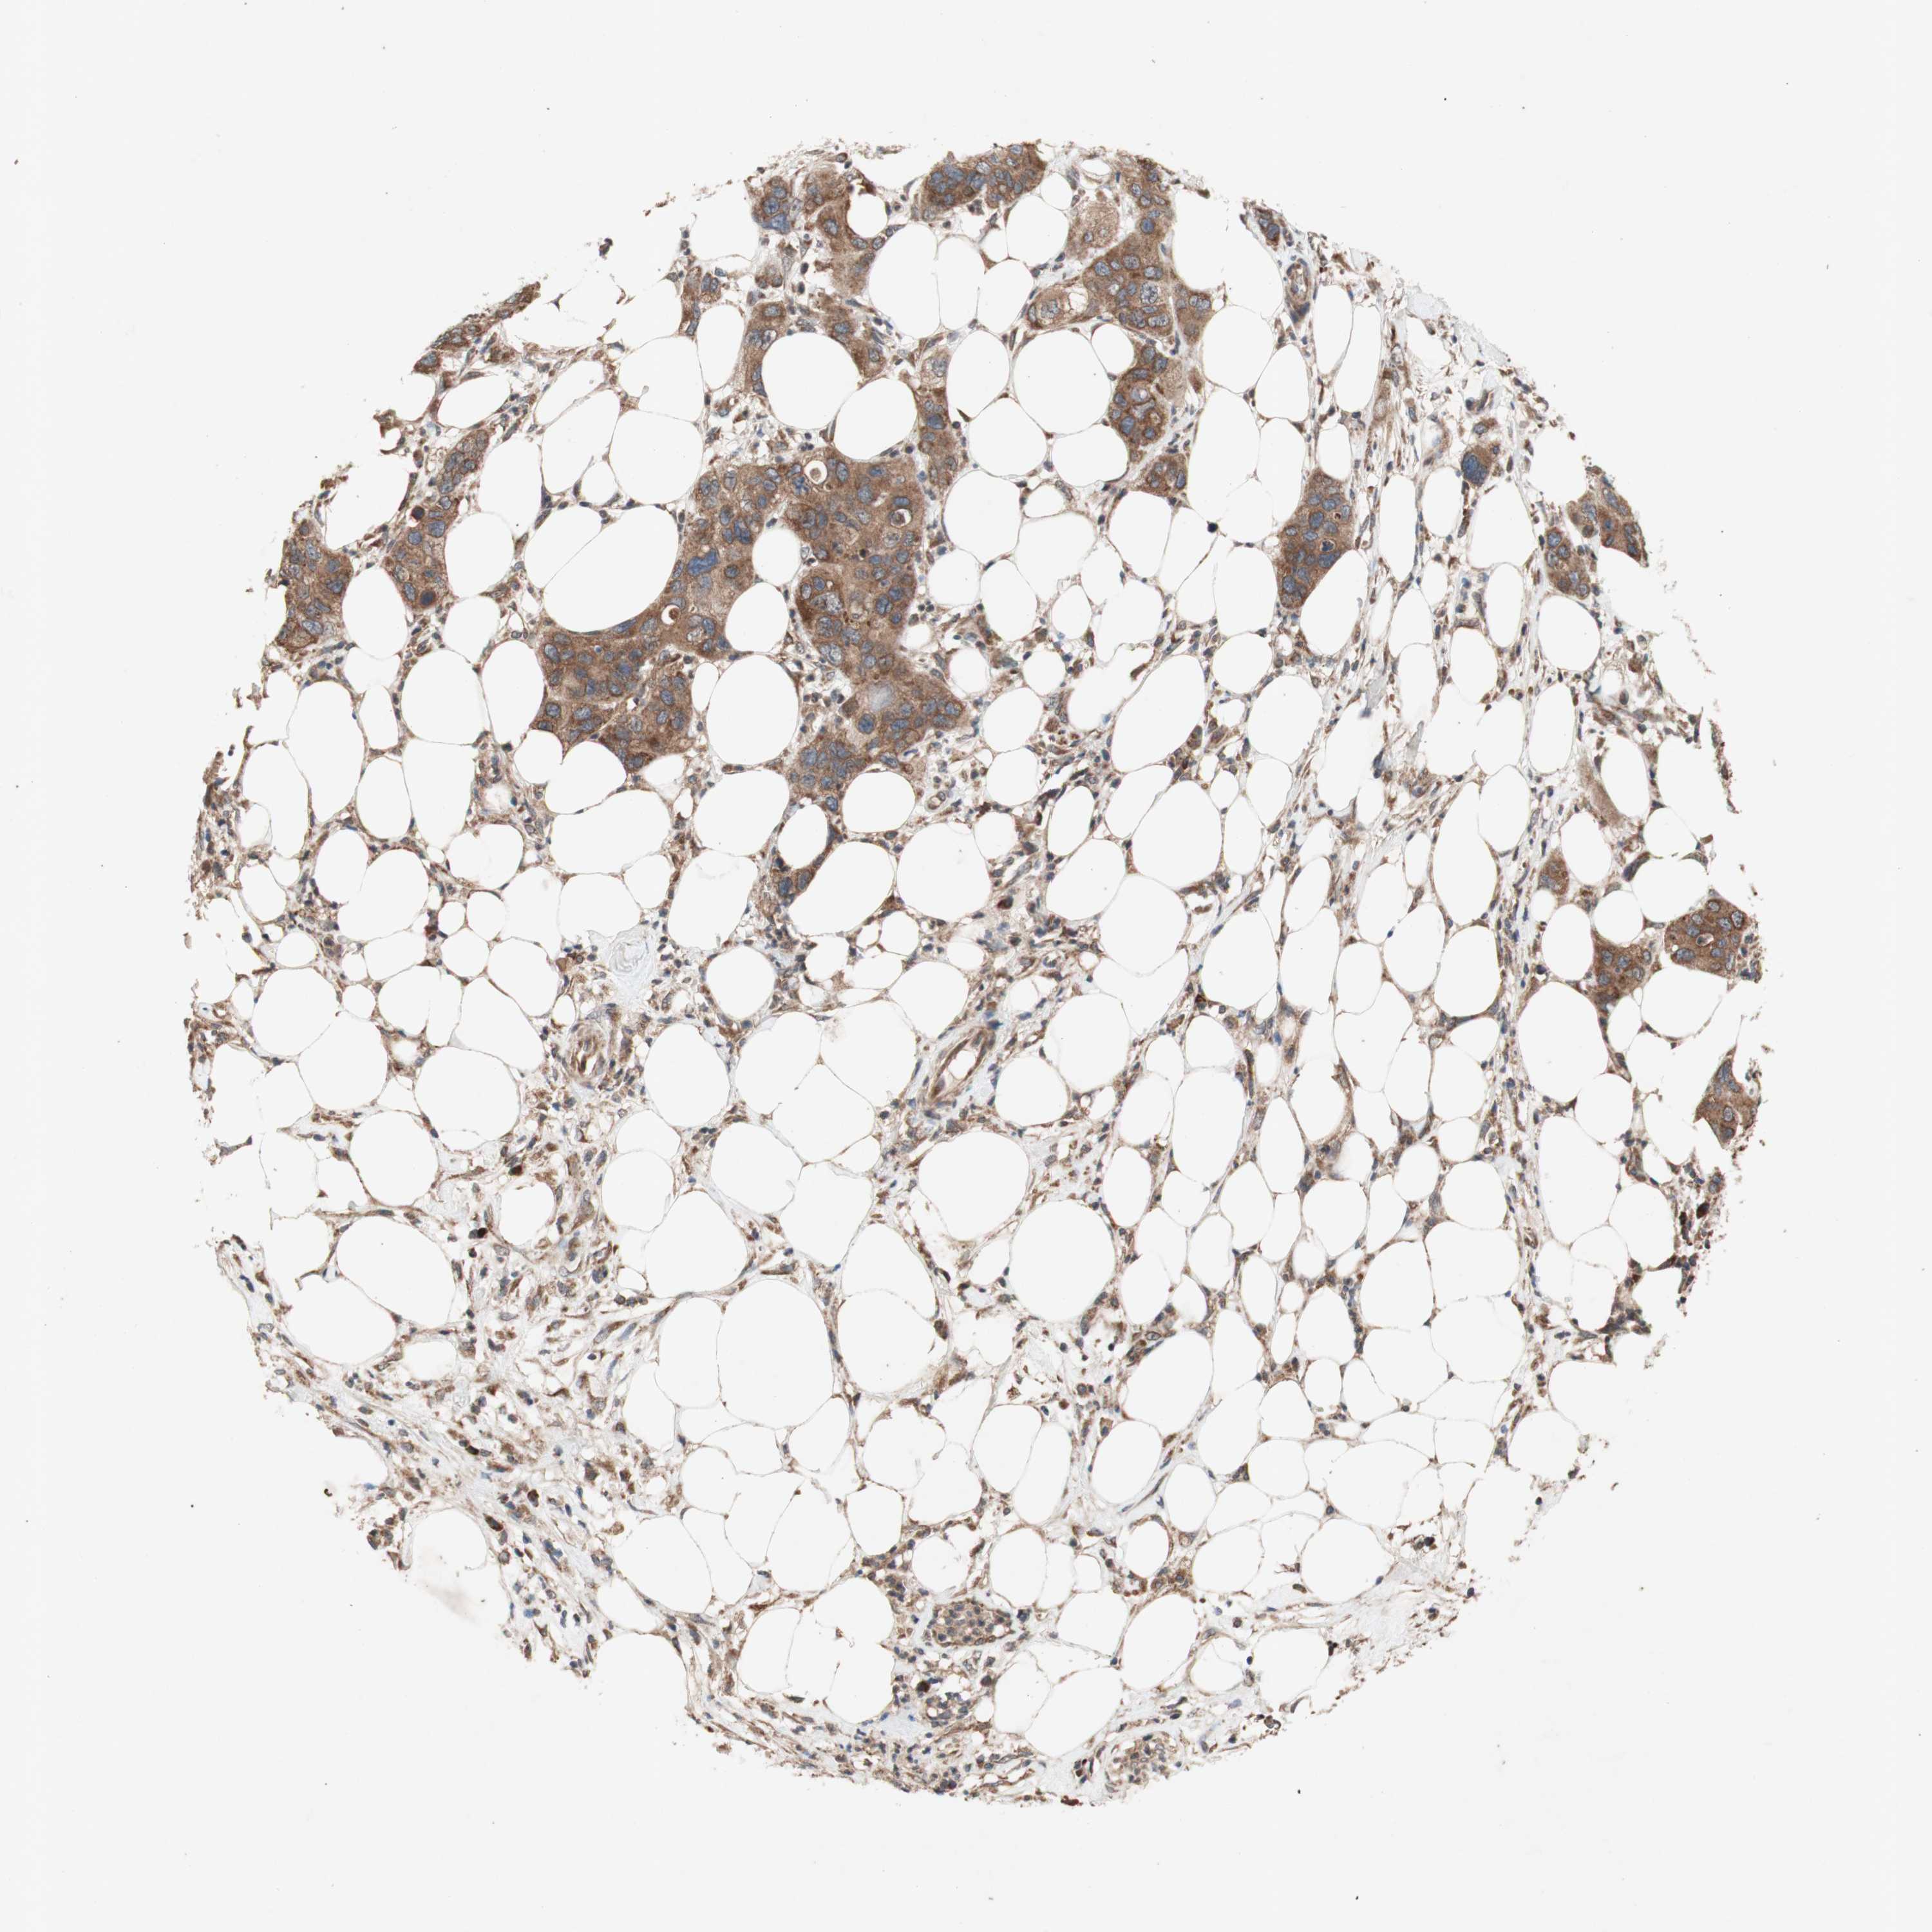

PANCREATIC CANCER - Protein expressioni

A mouse-over function shows sample information and annotation data. Click on an image to view it in a full screen mode. Samples can be filtered based on level of antibody staining by selecting one or several of the following categories: high, medium, low and not detected. The assay and annotation is described here.

Note that samples used for immunohistochemistry by the Human Protein Atlas do not correspond to samples in the TCGA dataset.

Antibody stainingi

Antibody staining in the annotated cell types in the current human tissue is reported as not detected, low, medium, or high, based on conventional immunohistochemistry profiling in selected tissues. This score is based on the combination of the staining intensity and fraction of stained cells.

Each image is clickable and will lead to virtual microscopy that enables deeper exploration of all samples and also displays staining intensity scores, fraction scores and subcellular localization as well as patient and tissue information for each sample.

Antibody HPA046841

Antibody HPA052867

Antibody CAB009746

Staining

High

Medium

Low

Not detected

Intensity

Strong

Moderate

Weak

Negative

Quantity

>75%

75%-25%

<25%

None

Location

Nuclear

Cytoplasmic/membranous

Cytoplasmic/membranous,nuclear

Adenocarcinoma, NOS

Adenocarcinoma, metastatic, NOS